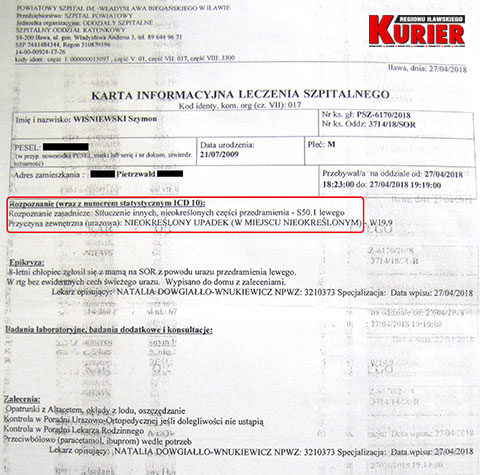

Karolina Wiśniewska z Pietrzwałdu 27 kwietnia 2018 roku zgłosiła się na iławski Szpitalny Oddział Ratunkowy z 8-letnim wówczas synem Szymonem, który po niefortunnym upadku na trawie skarżył się na ból łokcia.

– Zaniepokoiło mnie to, że pani doktor zleciła wykonanie prześwietlenia przedramienia, a nie łokcia, choć to z nim był największy problem – opowiadała nam wtedy kobieta. – Pani, która wykonywała prześwietlenie, na moją prośbę załapała łokieć, choć nie powinna. Powiedziała, że widzi złamanie, ale to lekarz zdecyduje, co dalej. Pani doktor stwierdziła jedynie stłuczenie. Zapytała Szymona, czy chce, żeby mu włożyć rękę w szynę. Syn zrobił duże oczy i był przerażony. Oczywiście tego nie chciał, więc tego nie zrobiono.

Chłopca wypisano do domu z zaleceniem wykonywania opatrunków z altacetem i okładów z lodu.

„W RTG bez ewidentnych cech świeżego urazu.

Zalecenia: opatrunki z Altacetem, okłady z lodu,

oszczędzanie” – czytamy w wypisie z iławskiego szpitala